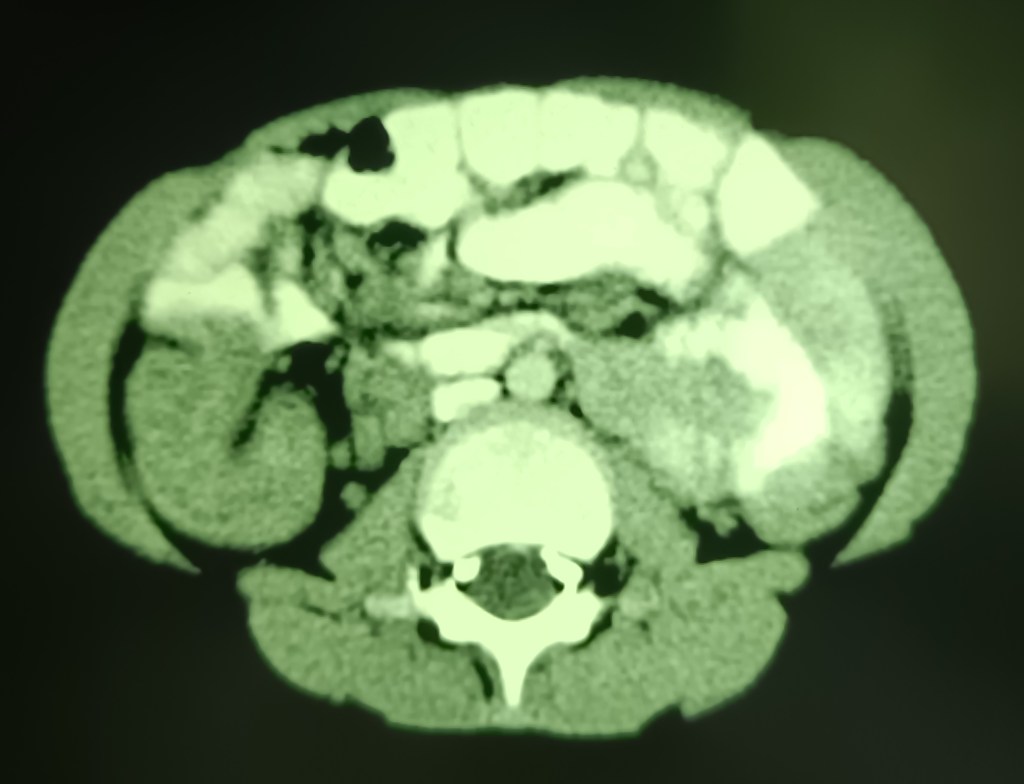

A 7 years old male child admitted with acute abdominal pain showed classic signs of target sign/doughnut sign/pseudo-kidney signs on ultrasound and a mass effect in right iliac fossa on CT. However, the child’s condition improved rapidly and in a few hours he became clinically better and pain free, suggesting spontaneous reduction of the intussusception. Recovered completely on conservative treatment and was not operated.